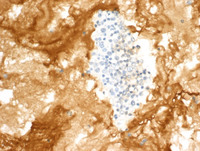

Figure 5: CD45 & CD30 in Primary Effusion Lymphoma

The large atypical cells are positive for CD45 (left) and for CD30 (low and high power; right and lower left). CD20 was negative.